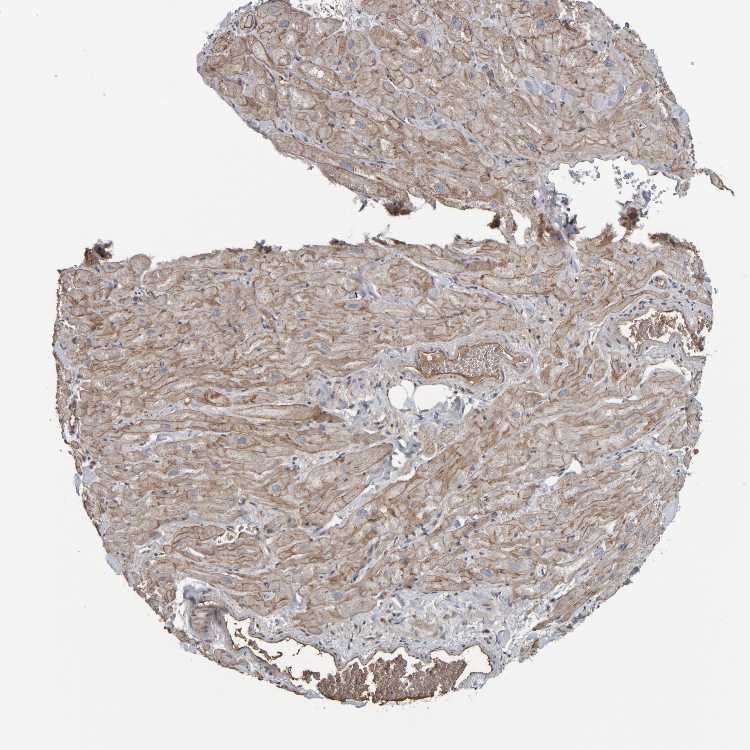

HEART MUSCLE - Antibody stainingi

Antibody staining in the annotated cell types in the current human tissue is reported as not detected, low, medium, or high, based on conventional immunohistochemistry profiling in selected tissues. This score is based on the combination of the staining intensity and fraction of stained cells.

Each image is clickable and will lead to virtual microscopy that enables deeper exploration of all samples and also displays staining intensity scores, fraction scores and subcellular localization as well as patient and tissue information for each sample.

Antibody HPA020973Antibody HPA020987Antibody HPA021021

Cardiomyocytes HighMediumMedium